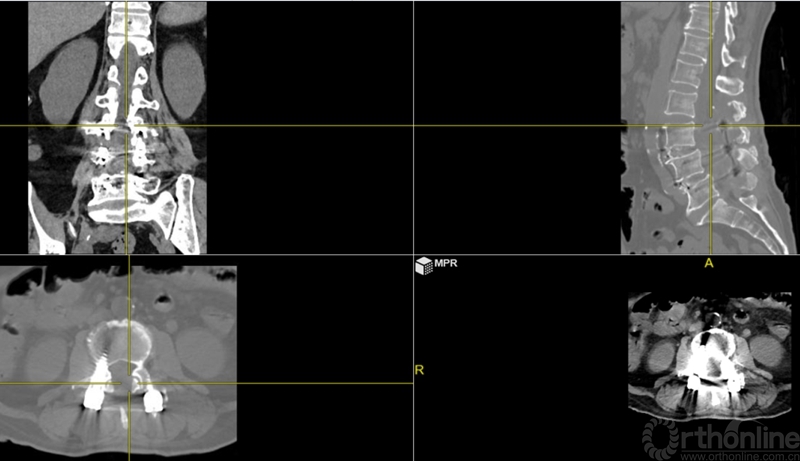

本文提供一例病例,高PI的腰椎显著前凸多节段的腰椎管狭窄症合并腰椎滑脱的患者(PI:57度,LL: 62度,图1、2、3),术前影像显示腰3-4、4-5椎管狭窄、椎体滑脱(图2、3),术前临床表现为右侧下肢麻木无力症状,术中接受了双节段MIS-TLIF手术。

图2:术前腰椎正侧位:腰3-4、4-5滑脱。腰椎矢状面顶椎腰23椎间隙,LL:62°,L34椎间隙与水平成角度21°,L45椎间隙与水平成角26°,椎间隙方向为术中工作通道方向。

图3:术前核磁:腰3-4、4-5椎管狭窄